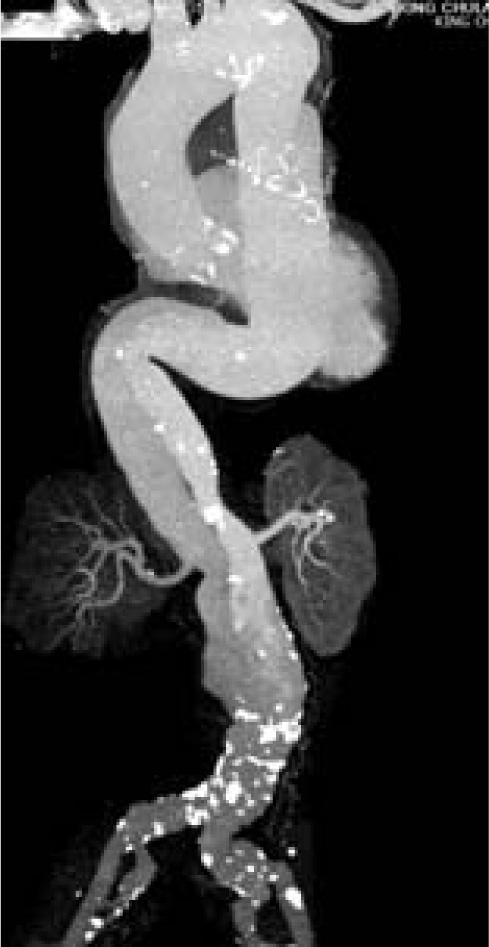

Figure 3